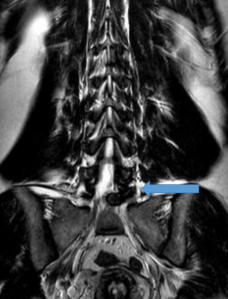

Hernia de disco lumbar extrusa L5 S1 (cortes

sagital y coronal en resonancia magnética)

Hernia de disco lumbar extrusa L5 S1 (cortes sagital y coronal en resonancia magnética)